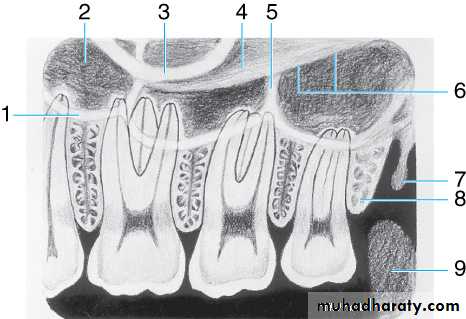

Drawing of maxillary molar area. Illustrated in the drawing are the (1) border (floor) of maxillary sinus, (2) maxillary sinus, (3) zygomatic process of maxilla, (4) zygoma, (5) septum in maxillary sinus, (6) lower border of zygomatic arch, (7) hamulus (hamular process), (8) maxillary tuberosity, and (9) coronoid process (mandible)

Radiographic Anatomy Basics

Radiograph of maxillary molar area. This radiograph shows (1) border (floor) of maxillary sinus, (2) maxillary sinus, (3) zygomatic process of maxilla, (4) zygoma, (5) lateral pterygoid plate, (6) lower border of zygomatic arch, (7) maxillary tuberosity, and (8) coronoid process of the mandible